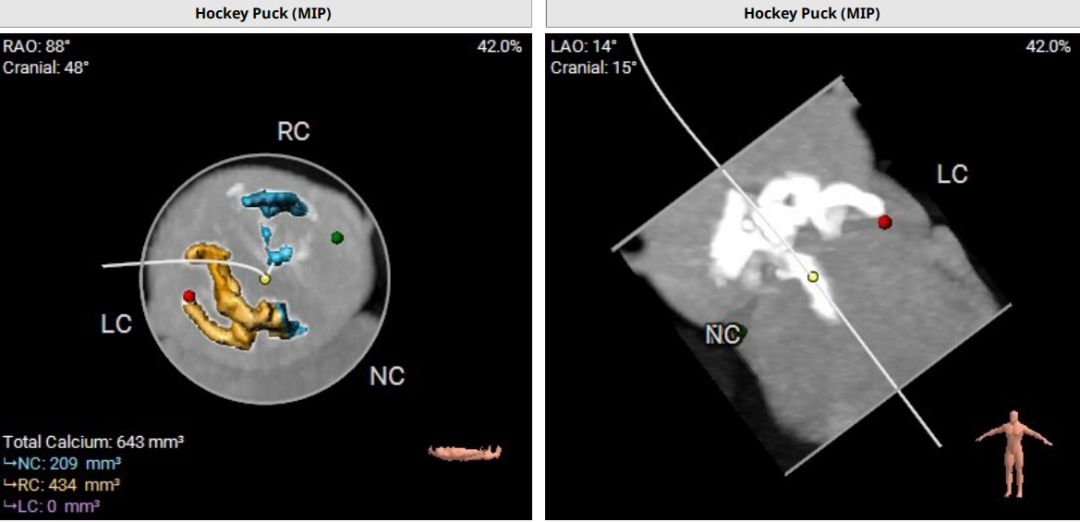

钙化评估:

球囊预扩风险评估: